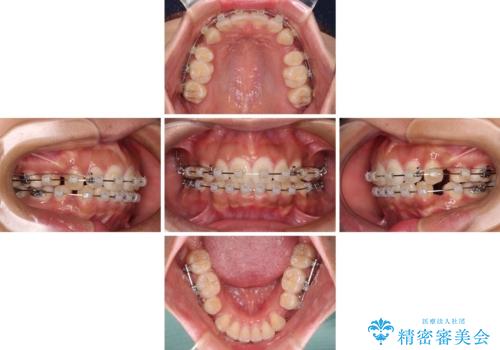

- クリアブラケット

- 2年6ヶ月

- 10-30回

口元の突出感を改善するため、上下左右第一小臼歯4本の抜歯を行い、ワイヤー装置による矯正治療を行うこととしました。